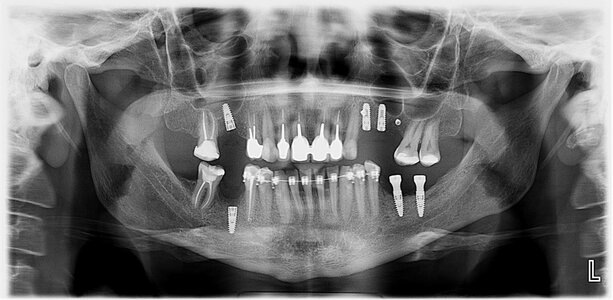

1) Панорамный снимок (ОПТГ) или ортопонтомограмма - это уже прошлый век. Подходит только для примерного планирования лечения, протезирования и удаления.

На нём обычно видны все зубы, но он имеет очень много искажений и наслоенных друг на друга разных рентгеноконтрастных структур, так как это двухмерный снимок И представляет собой по сути "рентгенологическую" фотографию зубов и костей черепа с очень длинной выдержкой ,чтобы за один снимок успеть объехать вас по кругу. По итогу мелкие детали рассмотреть на нем не возможно.

Не тратьте время и деньги на него.

Доза облучения при ОПТГ исследовании составляет не более 15–30 микрозиверт. При допустимом пороговом значении в 55 мкЗв для взрослого человека.